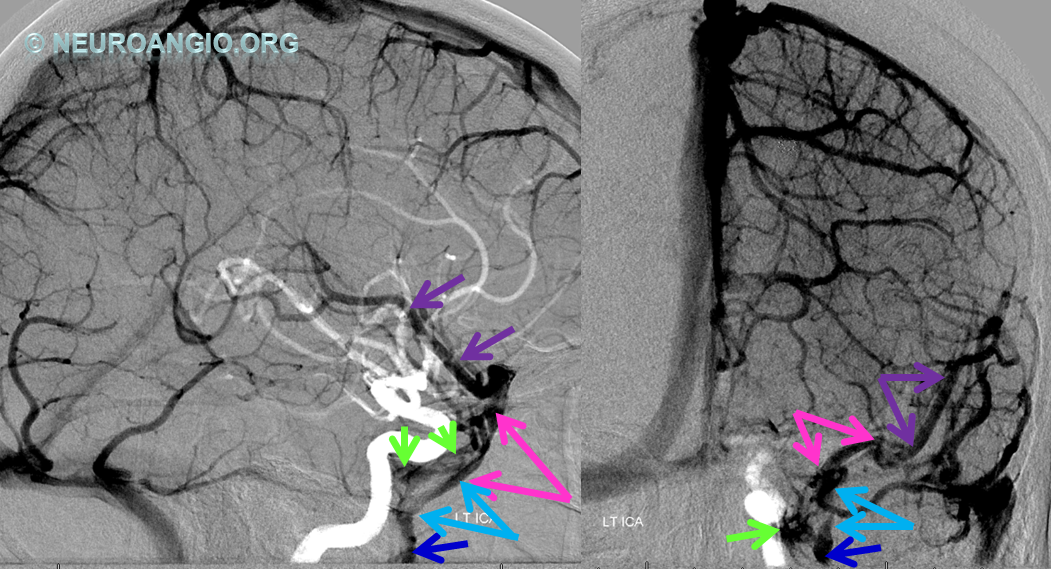

Following embolization, resection, recurrence (as frequently the case with childhood AVMs) and gamma-knife, things look good. Stereo, of course.

Following embolization, resection, recurrence (as frequently the case with childhood AVMs) and gamma-knife, things look good. Stereo, of course.